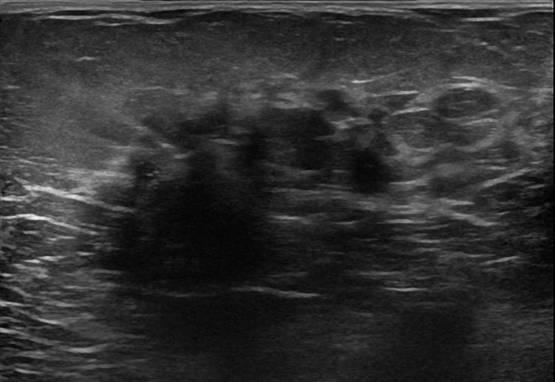

Ung thư vú

» Thông tin: Nữ giới – 58 tuổi.

» Lâm sàng: Khối tuyến vú.